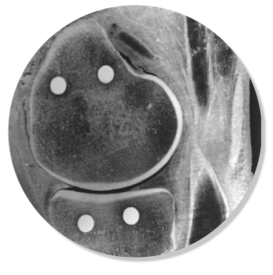

Question 5

Question

Which implant is shown in this image

Answer

• ZUK

• Cambridge

• Oxford

Question 6

How would you describe this implant?

• Fixed bearing unicompartmental

• Mobile bearing unicompartmental

• Fixed bearing total knee

• Mobile bearing total knee

Question 7

Which compartment is shown

• Trochlear

• Medial

• Lateral